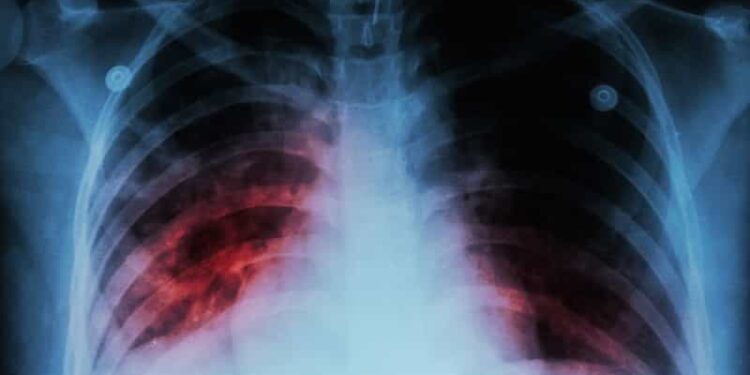

La noticia ahora a cambiado su enfoque de país, en este caso Corea del norte, ha detectado unas nuevas cepas de coronavirus que son 6 veces más peligrosas que la del Covid-19. La Organización Mundial de la Salud (OMS), junto con otras fuentes de salubridad a nivel mundial, han agrupado todas las cepas conocidas por letras. Esto para facilitar un lenguaje de su estudio universal. En total son 6 cepas, clasificadas de este modo: S, V, L, G, GH y GR. En el brote de Wuhan, China, estuvieron expuestas los clavos S y V. Sin embargo, en naciones como Estados Unidos y partes de Europa, según los estudios del genoma, se ha mostrado que en muchos casos  que prevalece el clavo GH. Y este ha llegado al país asiático Corea del norte.

Es un nuevo brote que vive el país, distinto al de los primeros meses de este año, el cual en los pacientes se podía encontrar las variantes S y V, al igual que en el resto de los contagiados a nivel mundial. Esta cepa es más peligrosa porque es mucho más mortal que las anteriores mencionadas. Y aunque todavía es mucho lo que se desconoce, las medidas deben tomarse más rápido y con más estrategias que las tomadas el la pandemia causada por el covid-19.